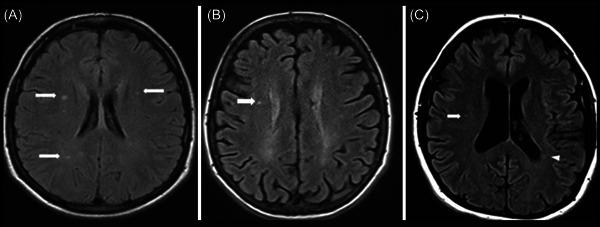

Comparison of recent updates in genetics, immunology, biomarkers, and neuroimaging of primary-progressive and relapsing-remitting multiple sclerosis and the role of ocrelizumab in the management of their refractory cases.

Primary-progressive multiple sclerosis (PPMS) and relapsing-remitting multiple sclerosis (RRMS) are two frequent multiple sclerosis (MS) subtypes that involve 10%-15% of patients. PPMS progresses slowly and is diagnosed later in life. Both subtypes are influenced by genetic and environmental factors such as smoking, obesity, and vitamin D insufficiency. Although there is no cure, ocrelizumab can reduce symptoms and delay disease development. RRMS is an autoimmune disease that causes inflammation, demyelination, and disability. Early detection, therapy, and lifestyle changes are critical. This study delves into genetics, immunology, biomarkers, neuroimaging, and the usefulness of ocrelizumab in the treatment of refractory patients of PPMS.